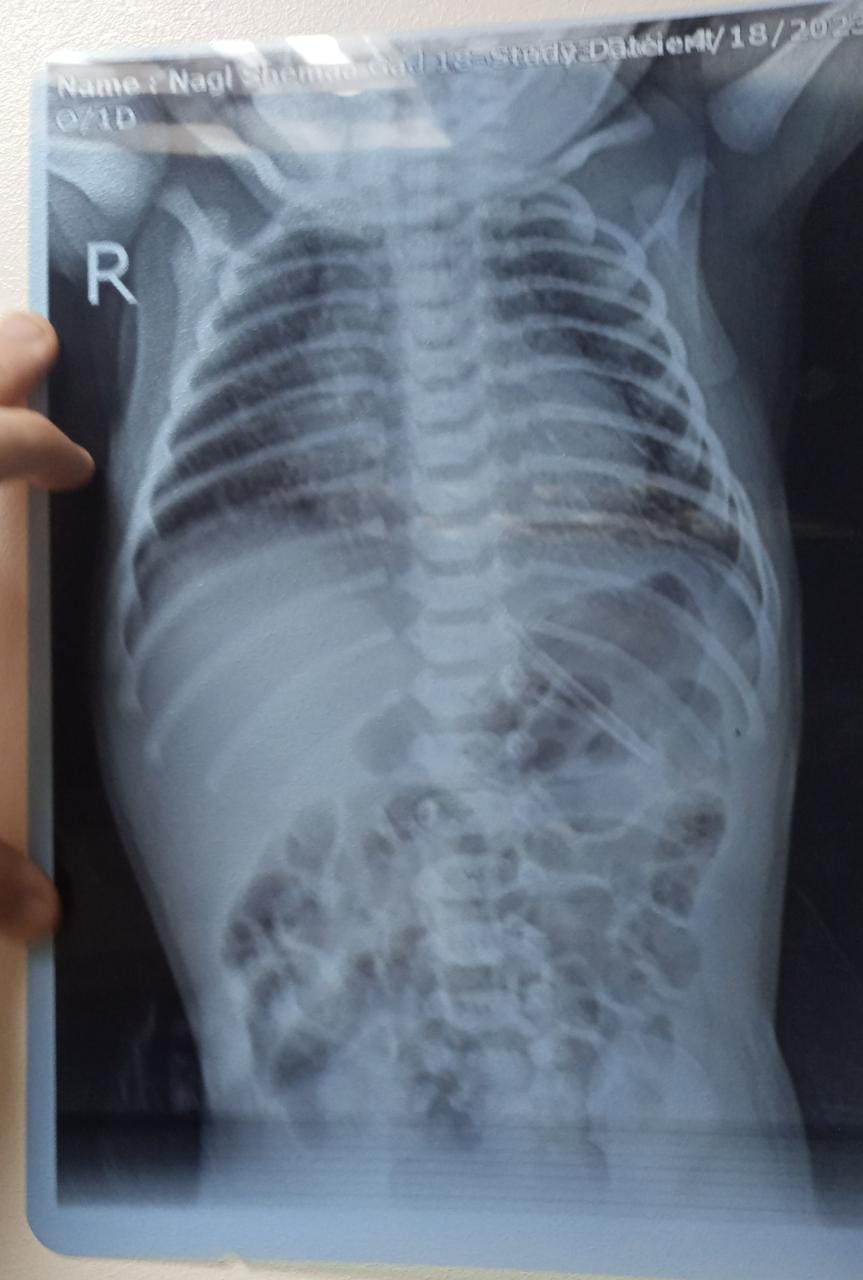

تعرضت الطفلة حور خالد، لإهمال طبي، وهي لم يتجاوز عمرها سوى أيام قليلة، حيث وٌلدت في الشهر الثامن من الحمل، مما أدى إلى عدم اكتمالها، وسرعان ما توجه الأب بها لحجز الصغيرة في حضانة داخل مركز طبي للنساء والتوليد، لتقديم كافة الرعاية الطبية لها، إلا أنه فوجئ بتدهور حالة الطفلة، نتيجة التركيب الخاطئ لجهاز طبي لها، نتج عنه تدهور حالتها الصحية سريعًا.

وأضاف: تم نقل الطفلة إلى المركز، ووضعها على جهاز السباب التنفسي، إلا أنها لم تتلقى أي رعاية طبية داخل المركز.

يستكمل الأب: كتبوا لي تقرير إن حالتها كويسة، اتخانقت معاهم تاني، لما عرفت إنهم ركبوا الجهاز غلط، منوهًا: أقروا أن الخطأ ارتكبه طبيب الجراحة وليس الأطفال.

وأشار الأب إلى أنه نقل الطفلة من المركز إلى مستشفى أخرى، وبدأت حالتها حاليًا في التحسن، ويعالج الأطباء ما تسبب فيه تركيب الجهاز الخاطئ.